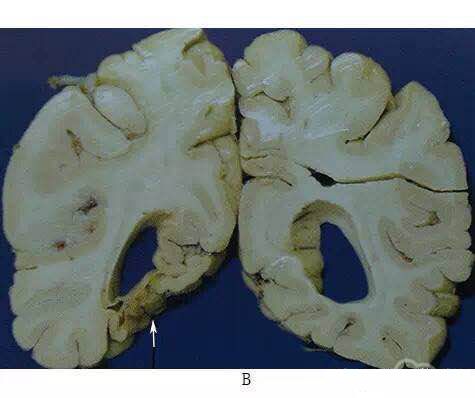

脑软化的病理改变

脑软化